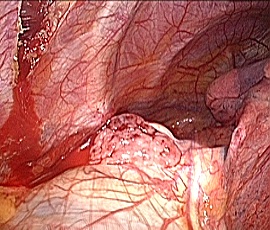

[胸腺腫] 手術:胸腔鏡下縦隔腫瘍手術

手術画像